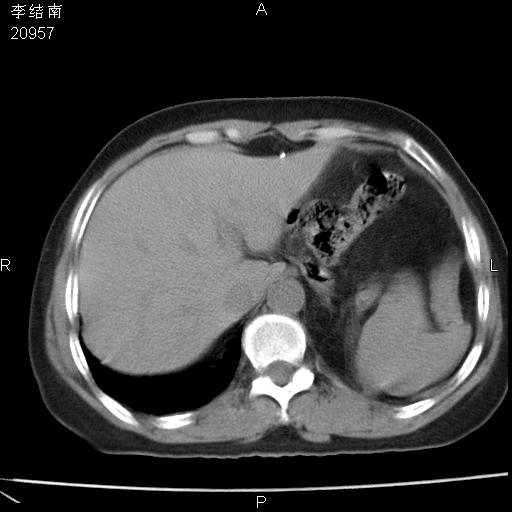

患者女,45岁,以右侧腰部包块来就诊,局部有压痛,皮肤颜色正常。因为是熟人扫的范围较大,患者有胆结石,胆源性胰腺炎病史。请大家看看,有手术病理。

可能大家觉得片子的质量不好,当时是做下腹部扫描,所以没有常规喝水,右腹壁的病灶当时是,密度不均有钙化影,局部骨质没见破坏,肝脏应该是受压的表现,所以当时考虑为腹壁的良性占位,各位老师考虑的神经源性肿瘤,我当时还真没想到,胰腺是胰腺炎治疗后改变.膈脚旁的混杂密度包快不好考虑什么,到上级医院做增强(腹部)+肺部平扫后,发现腹壁的病灶呈不均匀性强化局部可见囊性灶,当时考虑为腹壁结核,最具戏剧性的是膈脚旁的混杂密度灶确是胃的一部分,而腹壁的病灶确是脂肪瘤(简直不可思议)但是我亲眼所见在我们县医院开的.

很不好意思 ,患者后来手术切口裂开,临床医生作了病理证实是腹壁结核。

[病理诊断] CT13183腹壁结核!